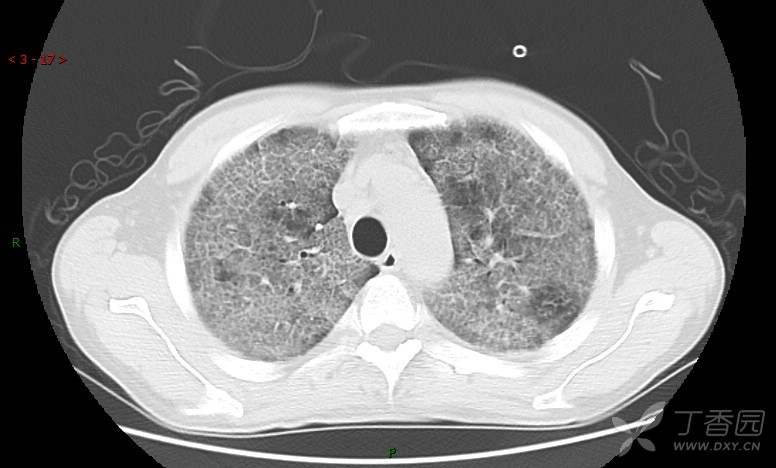

地图+铺路石征=PAP?那升高的CEA怎么说(病例3连发,附其他2例链接)

患者男,42岁,咳嗽半年余,加重伴憋喘2月余。

患者半年余前无明显诱因出现间断咳嗽,干咳为主,偶咳少量黄白痰,剧烈咳嗽或运动后可出现轻度憋喘,无高热、脓臭痰,无胸痛、咯血及晕厥,无低热乏力及盗汗,无心前区压榨感及夜间阵发性呼吸困难,初未在意,未予正规诊治。2月余前患者自觉上述症状较前加重,咳嗽、憋喘明显,黄白色粘痰略有增多,伴有发热,热前伴有畏寒、寒战,体温最高达38.9℃,先后就诊多家医院,入住重症监护室,未行气管插管,考虑“重症肺炎”,给予“美罗培南、复方磺胺甲噁唑”等药物抗感染,“卡泊芬净”抗真菌,并给予“甲泼尼龙”等药物治疗35天,经治疗后症状好转于2018-04-02出院。患者自出院后仅应用中药治疗(具体不详),并给予家庭氧疗,平素仍有间断咳嗽,咳少量黄白色粘痰,活动后憋喘明显,活动耐量差,以卧床为主。

肺内弥漫性网状结节影,PET-CT却无阳性病灶,这是?(附其他2例链接)